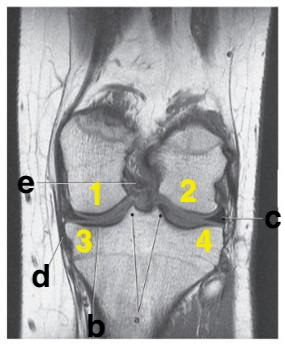

What is # 4?

What imaging plane is this?

coronal

medial collateral ligament

Where is the tibial plateau?

3 and 4